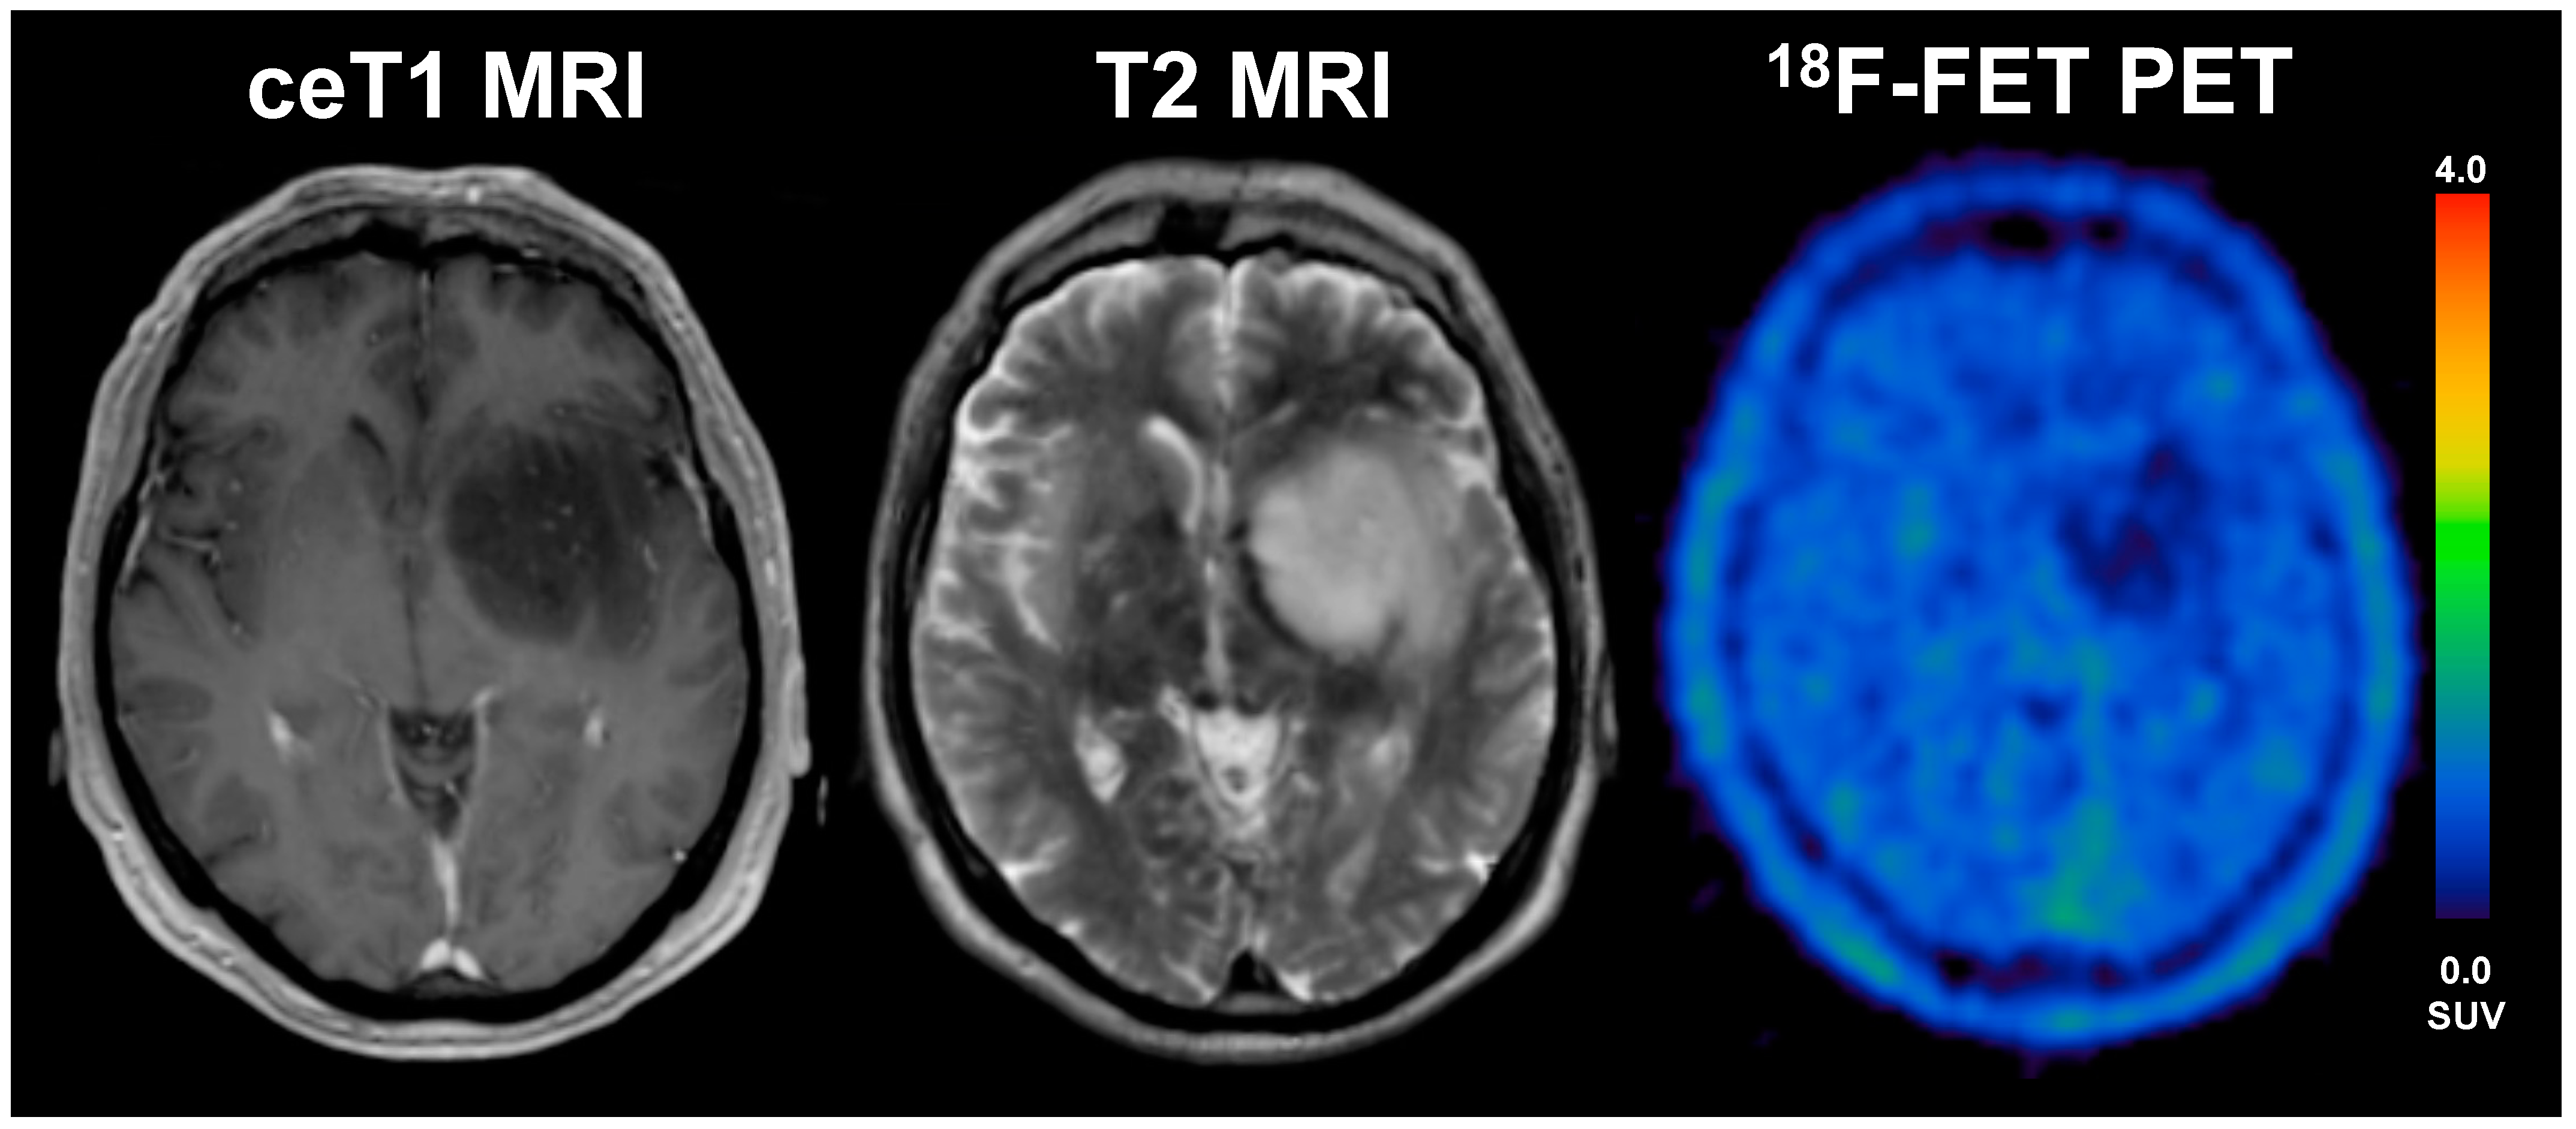

Figure 3.

A 33-year old male patient with glioblastoma (WHO grade IV, IDH wildtype, MGMT methylated) and an overall survival of 47 months (LTS). The diameter of CE on T1 MRI was 17 mm, volume of CE was 28 mL, the BTV in FET-PET was 16 mL, the TTPmin was 17.5 min and TBRmax 4.1. The patient underwent radio-chemotherapy.